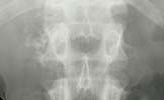

146) A 65 year old Hispanic man presents to your office for intermittent abdominal discomfort. He is afebrile and his he physical examination is benign.

A plain x-ray of his abdomen is obtained , the film is shown below :

The most likely complication that this patient is likely to develop: